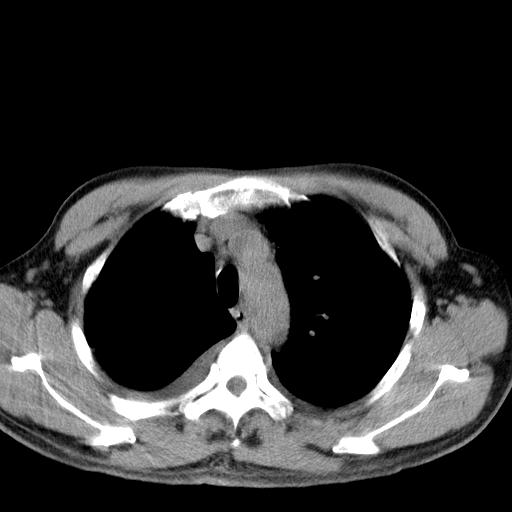

以下是引用zjzjr在2010-3-21 17:39:00的发言:[br]右下中心型肺癌并阻塞性肺炎/不张,纵膈淋巴结肿大,右侧大量胸腔积液,左侧少量胸腔积液

以下是引用zxl51642在2010-3-21 17:06:00的发言:[br]右下中心型肺癌并阻塞性肺炎/不张,纵膈淋巴结肿大,右侧大量胸腔积液,左侧少量胸腔积液,少量腹水。建议纤维支气管镜进一步检查。